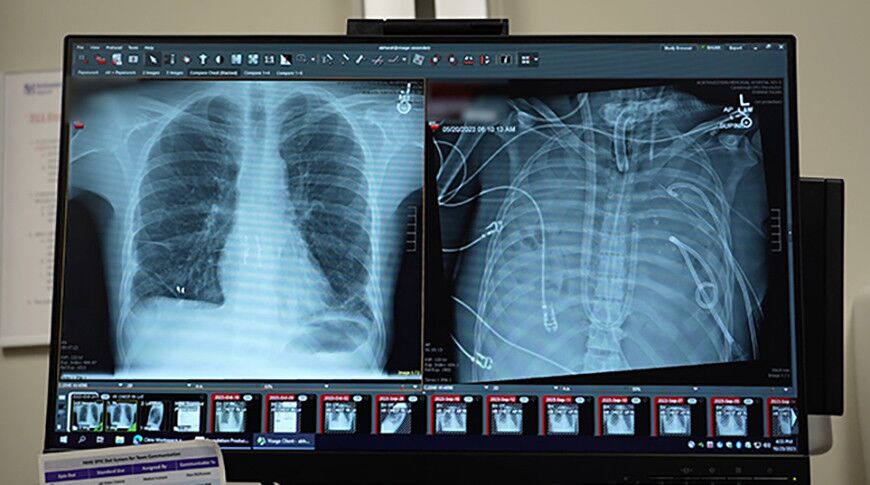

Amerikaly hirurglar näsagy iki gije-gündizläp öýkensiz diri saklamagy başardylar. Lukmaçylygyň bu haýran galdyryjy üstünligi barada ScienceAlert ylmy neşirde has içgin gürrüň berilýär.

33 ýaşly erkek adam agyr dümewden soň ölüm bilen ýaşaýyşyň arasynda galýar. Infeksiýa öýkenleri hatardan çykaryp, pnewmoniýanyň, sepsisiň we ýiti bronhial ýetmezçiliginiň döremegine sebäp bolýar. Bejerginiň peýdasyndan geçen, gaýta öýkenleriň özi ýokançlygyň çeşmesine öwrülýär. Has takygy, olary bedende saklamak, gönümel ölümi aňladýan derejä baryp ýetýär.

Şunlukda hirurglar ýaňy-ýakyna çenli mümkin däl diýlip hasap edilen çözgüde gelýärler we iki öýkeni hem bütinleý aýyrýarlar. Näsagy bolsa ABŞ-nyň Demirgazyk-Günbatar uniwersitetinde işlenip düzülen doly emeli öýken ulgamyna (TAL) çatýarlar. Ol gany kislorod bilen baýlaşdyryp, gan aýlanyşygyny dolandyrýar we ýürege düşýän agramy azaldýar.

Şeýlelikde, bu geň ykbally hassa, tä donor agzalary tapylýança 48 sagatlap öýkensiz ýaşaýar. Ondan soň bolsa transplantasiýa amala aşyrylýar.

Bu wakadan bäri iki ýyldan gowrak wagt geçen hem bolsa, lukmanlar oturdylan öýkenleriň kadaly işleýändigini aýdýarlar.

Bu ýagdaý lukmançylykda örän uly öňegidişlik hasap edilýär. Çünki bu tehnologiýa öňler oturtmak mümkin däl hasap edilen öýkeni-de transplantasiýa edip bolýandygyny aňladyp, öýkeni agyr hem ýiti şikesli näsaglarda sagalmaga uly umyt döredýär.